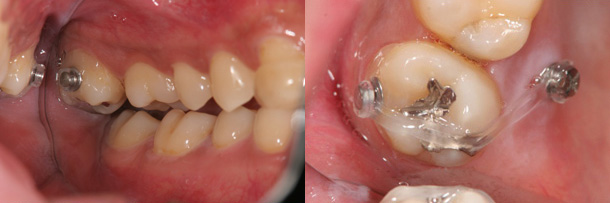

症例:第二大臼歯のすれちがった咬み合わせを改善

主訴:顎が痛い 奥歯が咬んでない

診断:上顎右側第二大臼歯の交叉咬合

年齢:24歳

装置:歯科矯正用アンカースクリュー

治療期間:3か月

抜歯:なし

費用:30,000円+税

矯正前

矯正後